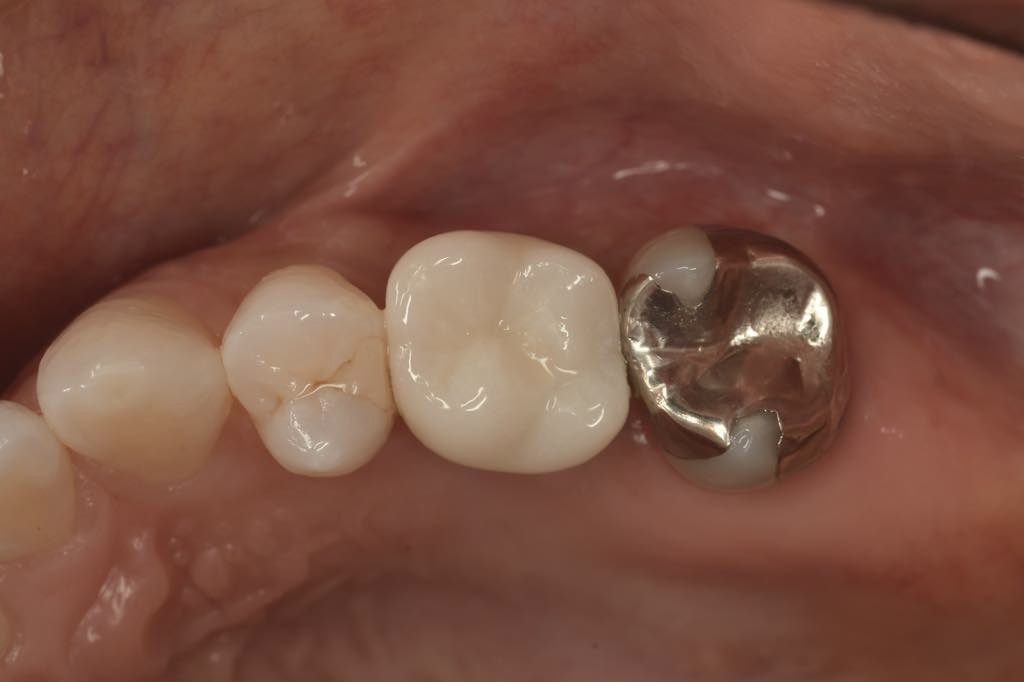

CASE 04

| 主訴 | 歯がないところにインプラントをして欲しい |

| 治療内容 | 左上4番 インプラント |

| 治療回数 | 8回 |

| 治療費用 | ¥412,000 |

| 想定される副作用 | 腫れ、痛み |